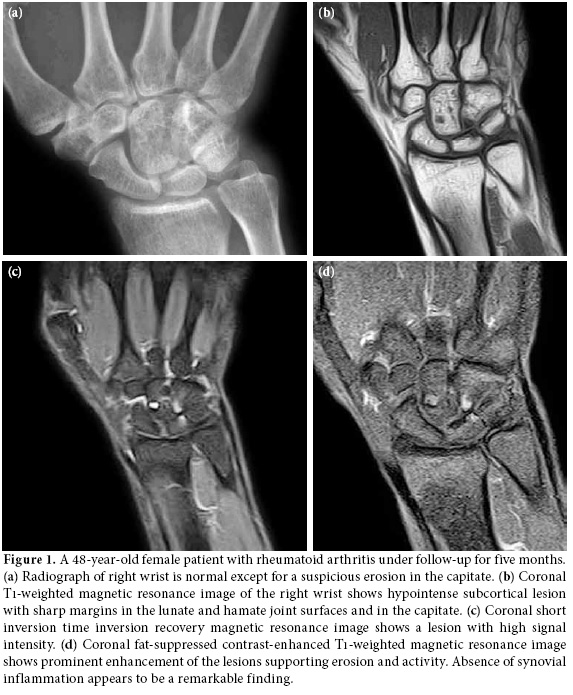

All the cases had a radiograph which was either normal or with suspicious erosions. Magnetic resonance imaging showed 73 (81.1%) bone erosions over different sites in carpal bones, four (4.4%) in distal radius, four (4.4%) in distal ulna, and nine (10%) in proximal metacarpal heads. All the erosions were single or multiple and non-adjacent focal while showing low signal intensity on T1-weighted images with contrast enhancement and high intensity signals on T2-weighted images (Figure 1-3). No bone marrow edema signs which are seen in the advanced stages of the disease as diffuse or converging signal changes were observed. Capitate was the site having the highest number of erosions with 20 (27.3%), followedby triquetral, scaphoid, lunate, trapezoid, hamate, trapezium, and pisiform having 18 (24.6%), 11 (15%), eight (10.9%), six (8.2%), six (8.2%), three (4.1%), and one (1.3%) erosion, respectively.

On MRIs, erosions appear as trabecular bone loss with sharp margins accompanied by cortical defect. Erosions can be more clearly observed following intravenous gadolinium injection.

Bone erosions

Presence of bone erosions were evaluated in 15 different anatomical regions (8 carpal bones, distal radius, distal ulna, 5 metacarpal heads). All the erosions were defined as single or multiple focal areas with sharp and regular margins causing defects in the cortical and subcortical bone marrows. Lesions with low signal intensity on T1-weighted images, high signal intensity on T2-weighted images and enhanced after contrast material administration were identified as bone erosions.